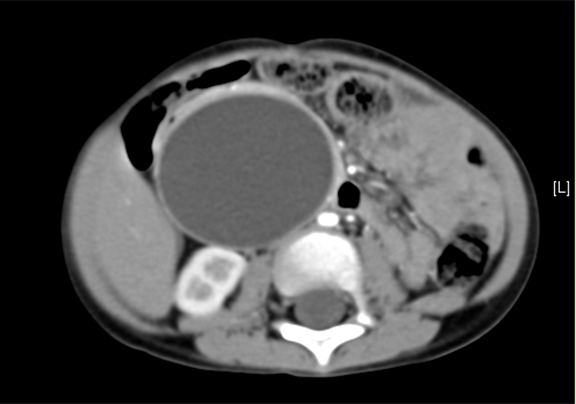

术前CT检查:

动脉期

腹部CT 增强:1. 肝内外胆管扩张,考虑胆总管囊肿并胆系扩张可能性大2. 胆囊结石。